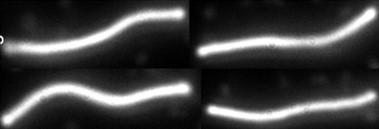

Borelioza, czyli choroba z Lyme, jest najczęściej występującym na świecie zakażeniem przenoszonym ze zwierząt na ludzi, a zarazem najczęstszą bakteryjną chorobą przenoszoną przez kleszcze. Czynnik etiologiczny choroby stanowi bakteria Borrelia burgdorferi – bardzo ruchliwa, spiralnie skręcona bakteria z rodzaju Borrelia, należąca do krętków (Spirochaeta), o długości około 15 mikrometrów i szerokości 0,2 mikrometra. Nazywana bywa również „parazytą teflonowym”, ponieważ jej powierzchnia pokryta jest specjalną substancją zawierającą niewiele antygenów powierzchniowych, przez co przeciwciała ochronne organizmu trudniej się do niej przyłączają. Bez leczenia bakteria może przetrwać w organizmie przez lata, a nawet dziesięciolecia, dzięki niezwykłej zdolności adaptacji, skutecznej obronie oraz obecności form wegetatywnych, tzw. gemm